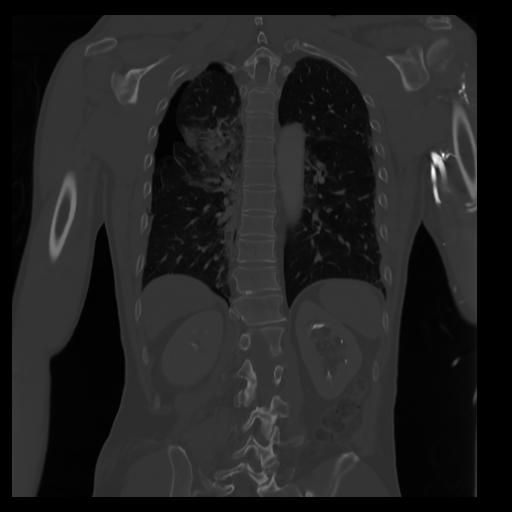

29 CUERPO,CE,Coronal,3.000,CUERPO,Coronal,